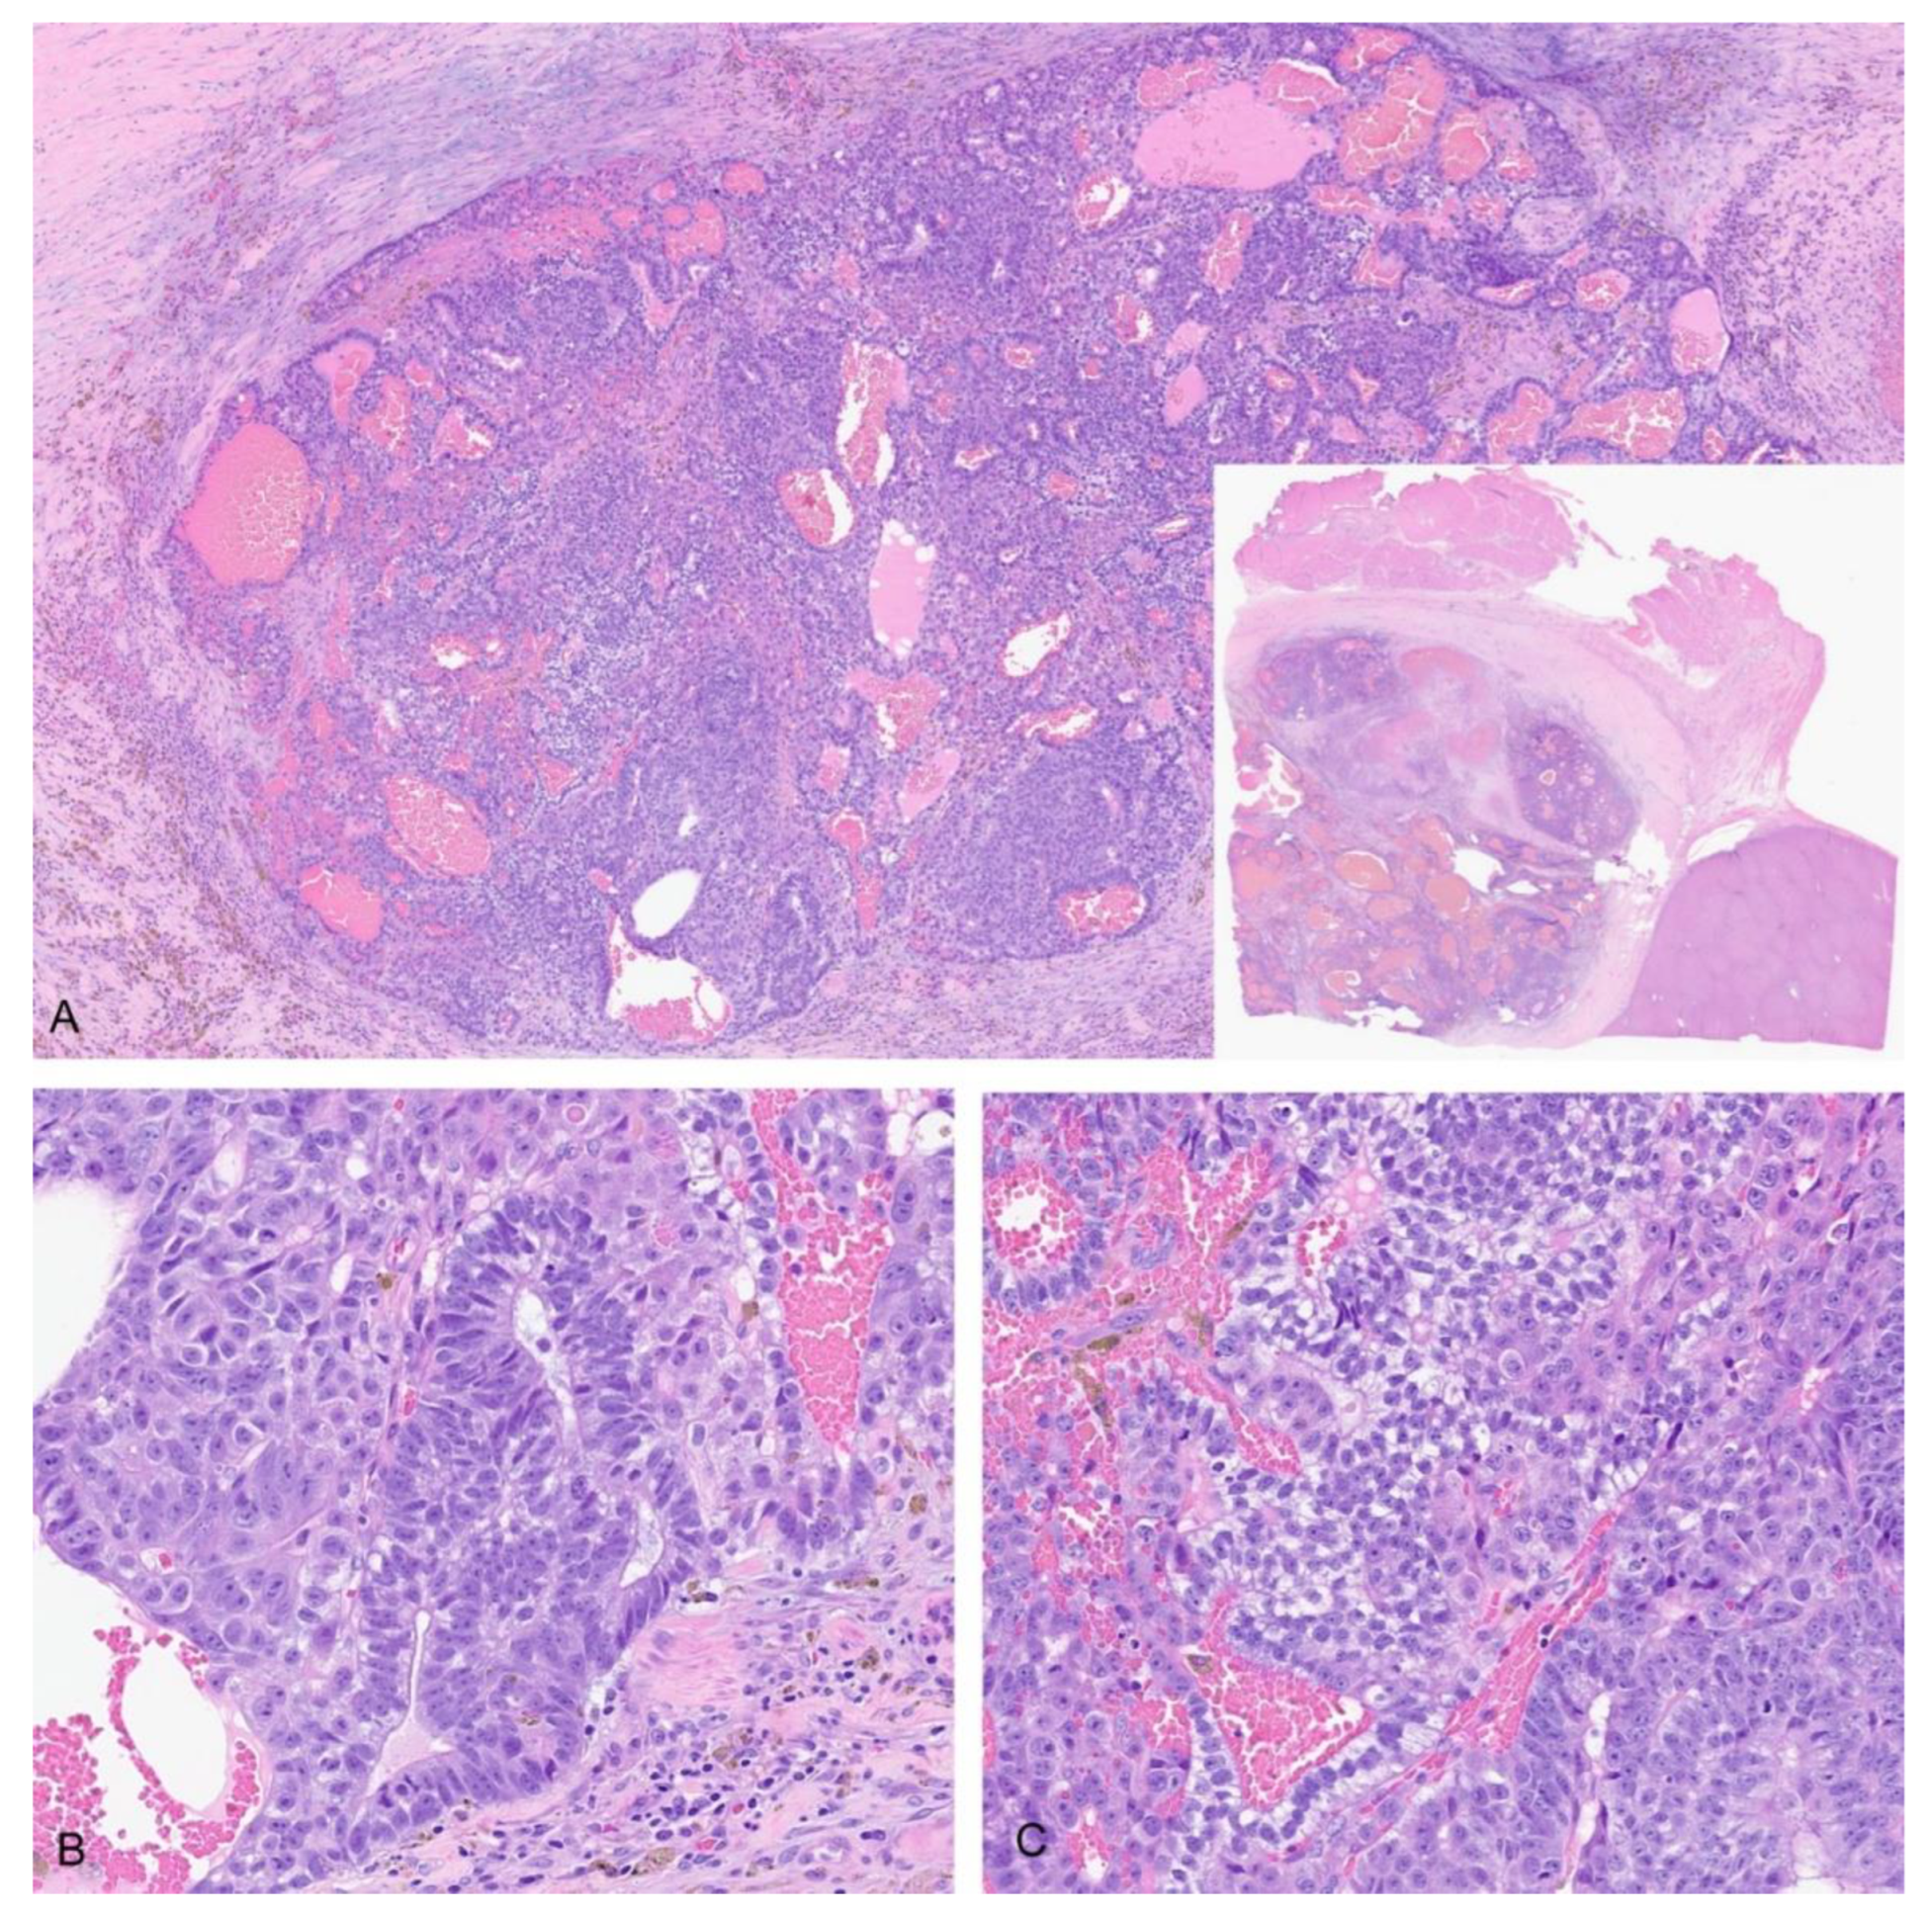

3.2.1. Histology